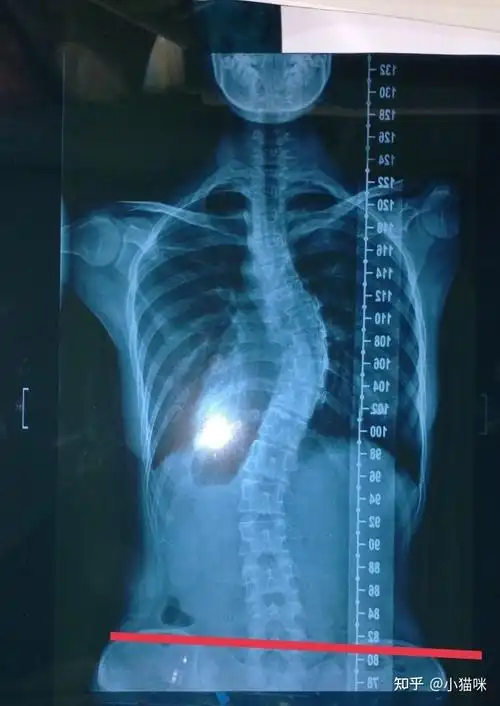

青少年脊柱侧弯患者脱支具的条件有哪些

脊柱弯曲角度≥10度就被定义为脊柱侧弯